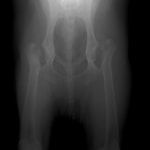

PennHIP法を実施した症例のレントゲン写真

PennHIP法(ストレスX線撮影法)

股関節の緩みを客観的に評価することが可能です。University of Pennsylvania Improvement Program (PennHIP) に評価を依頼する方法です。この機関に依頼する場合、Penn HIP により認定されている獣医師により撮影された特別な撮影像が必要となります。当院では、PennHIP 認定獣医師の資格がありますので撮影が可能です。4ヵ月齢から評価可能ですので、股関節形成不全の発症の有無を知りたい場合にも利用可能です。(PennHIP法の詳しい説明はコチラ)